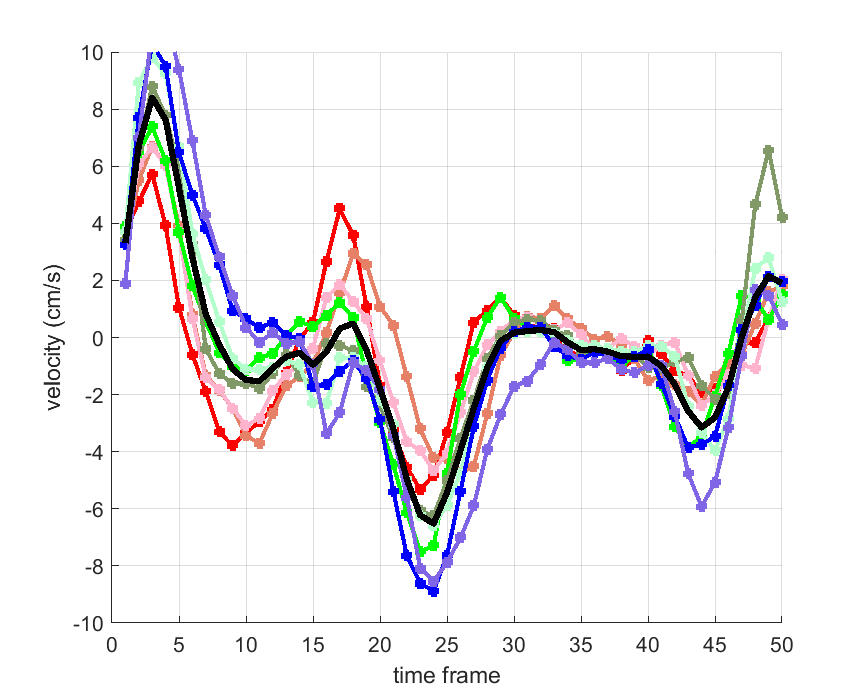

Time courses of the estimated translational component per subject, frame, slice and volume along the 3 velocity directions x, y and z are presented in Fig.6 - Fig.8.